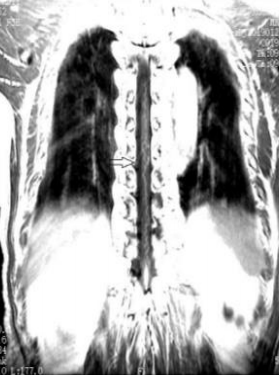

病例1

患者女,41岁。突发双下肢无力6小时。

答案:脊髓血管畸形并出血。造影及手术结果如下。

脊髓出血发病急,临床少见,血管畸形是脊髓出血的主要原因。主要表现为剧烈胸腰背部疼痛及截瘫,感觉障碍及括约肌功能障碍。脊髓出血与急性脊髓炎、脊髓梗死相互鉴别。脊髓炎发病前可有呼吸道或消化道感染等诱因,神经根刺激症状不明显,MRI检查可见T2WI横贯性的异常高信号。脊髓梗死可急性或亚急性发病,多发生在中老年人,以脊髓前动脉梗塞多见,运动障碍明显,感觉障碍轻微或缺失,MRI检查T2WI像可见脊髓前动脉供血区高信号,后索多不受累。